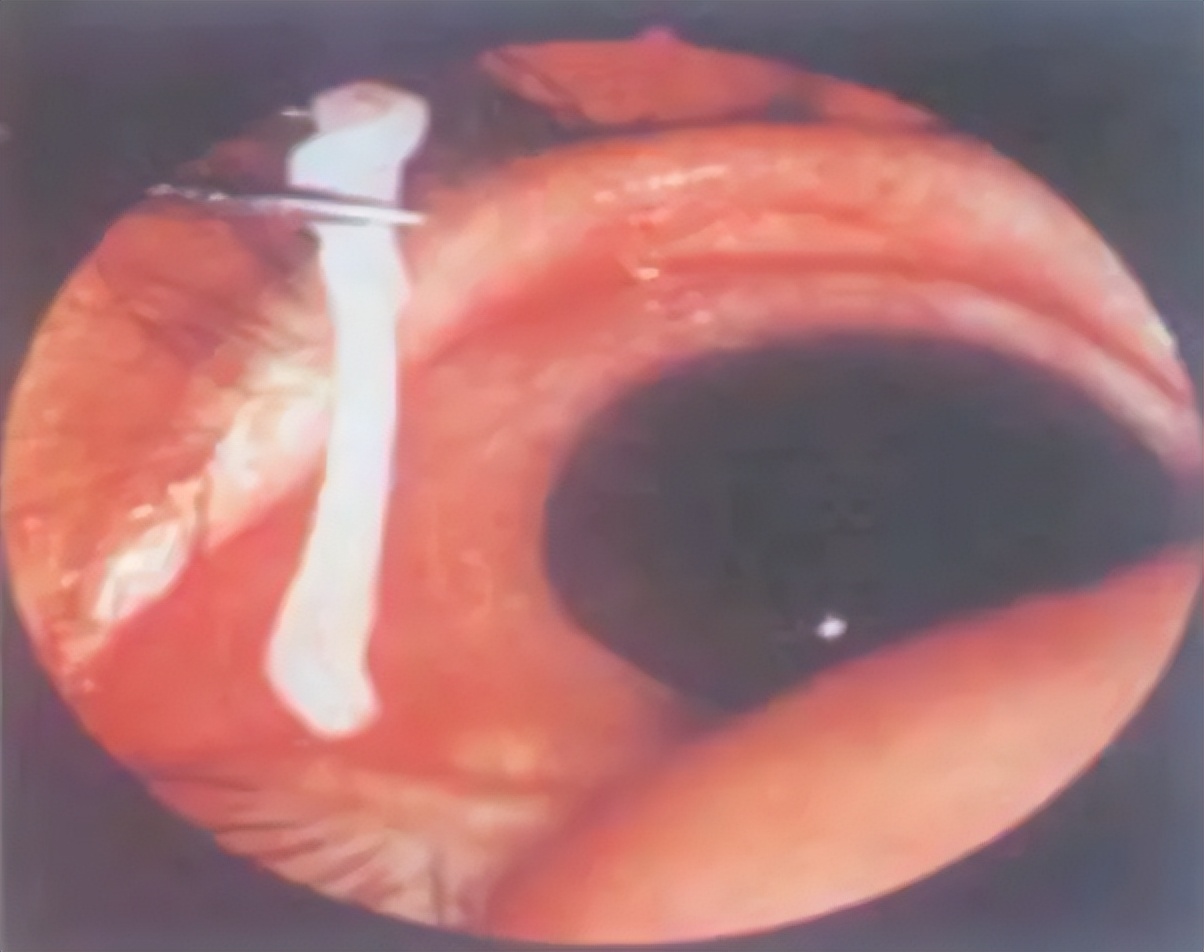

一般,肠道寄生虫可以通过粪便检查出来;当然,做其他检查时也可能会发现体内的寄生虫,比如做胃肠镜时,能够发现十二指肠和肠道里的虫。